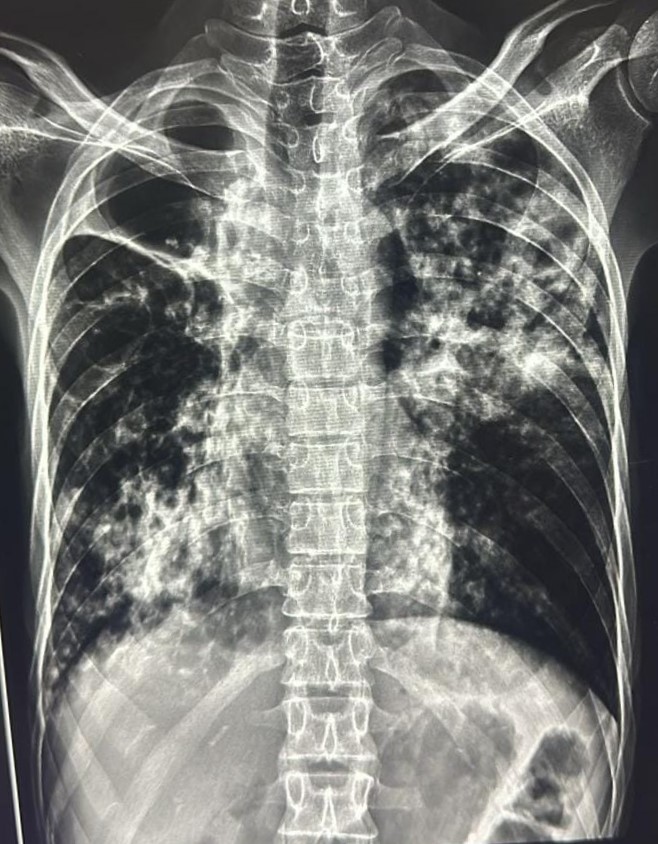

| 111 | IGGMC, Nagpur, Nagpur | P2 | 29-4361 | Sunil Shahu | Consent taken on Paper | 53 Yrs. |

Provisional Diag : Pulmonary Tuberculosis Follow-Up

Final Diag : TB Infiltration |

TB Case (Confirmed) | Bilateral Upper Zone& Mid Zone TB Infiltration | Abnormality visible on x-ray |